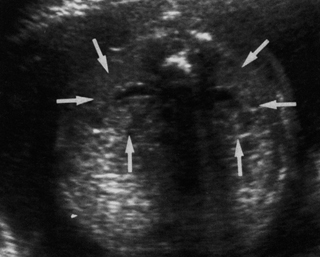

Επιμήκεις και εγκάρσιες τομές μπορούν να χρησιμοποιηθούν για τη μελέτη των νεφρών

(εικόνα 1).

| Εικόνα 1. Φυσιολογική απεικόνιση των νεφρών. | Εικόνα 2. Φυσιολογική